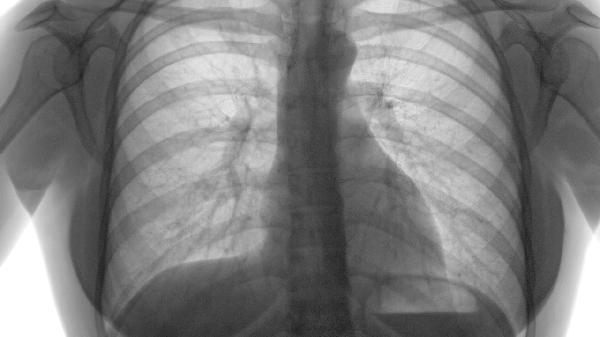

適用于靜息狀態(tài)下血氧飽和度低于88%的重度患者。長期家庭氧療每日≥15小時可糾正低氧血癥,降低肺動脈高壓風(fēng)險。需通過動脈血氣分析調(diào)整氧流量,目標(biāo)維持SpO2在90%-93%之間,避免二氧化碳潴留加重。